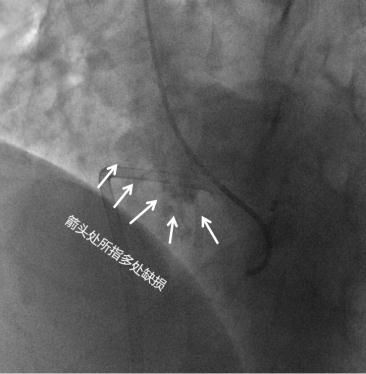

在手术中,介入导管进入陈某心脏后,医生们惊奇地发现,陈女士的室间隔竟然是5个洞,而且室间隔上有膨出,膨出部分外形像瘤子,5个孔洞全长在膨出的室间隔组织上,不大的室间隔上全都是孔洞,就跟筛子一般。

【 间隔|心脏有5个洞!孕妇懵了:我怎么能安稳活这么多年?】陈女士室间隔上的5个孔洞

室间隔膨出瘤伴筛孔型缺损不但罕见,而且手术治疗难度极高,妥妥的高难复杂手术。幸好新发现的几个孔洞也都不大,直径都没超过5毫米,而且医生们也是经验丰富,虽然手术难度上升好几个等级,但在医生们的努力下,最终陈女士的室间隔缺损还是得到完美修补。